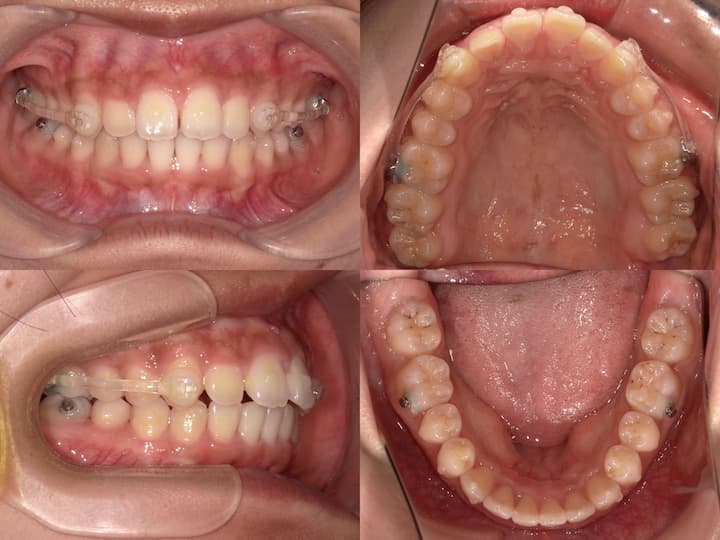

本症例は、叢生および口唇部の突出感を主訴とする患者様に対し、ハーフリンガル矯正装置(上顎舌側・下顎唇側)を使用して治療を行いました。

初診時の口腔内所見および頭部X線規格写真分析より、以下の所見が認められました。・上下顎前歯部の叢生

・口唇部の突出感

・AngleⅠ級臼歯関係(良好な臼歯関係)

・下顎骨の後方位(ハイアングル症例)

・下顎下縁平面角の増大